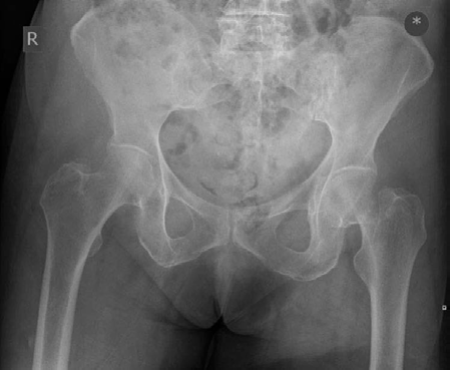

A 45-year-old male presents after a high-energy fall, sustaining a posterior wall acetabular fracture with a congruent reduction after closed hip dislocation. Post-reduction radiographs show no incarcerated fragments. Which of the following is the most appropriate management strategy?

For isolated posterior wall acetabular fractures that are congruent and stable after closed reduction of a hip dislocation, non-operative management with protected weight-bearing and restricted range of motion is a recognized option. Instability is typically assessed with stress radiographs or dynamic fluoroscopy after reduction. If stable, close monitoring for secondary displacement or late instability is crucial. Surgical indications usually include persistent instability, incarcerated fragments, or significant displacement. Immediate ORIF is typically reserved for unstable fractures or those with incarcerated fragments. Skeletal traction is less commonly used for these stable fracture patterns. Hip arthroplasty is not indicated primarily for this injury pattern without pre-existing arthritis or severe head damage. A CT scan is usually performed initially to assess the fracture pattern and rule out incarcerated fragments, but repeating it in 24 hours without clinical change is not the primary management.